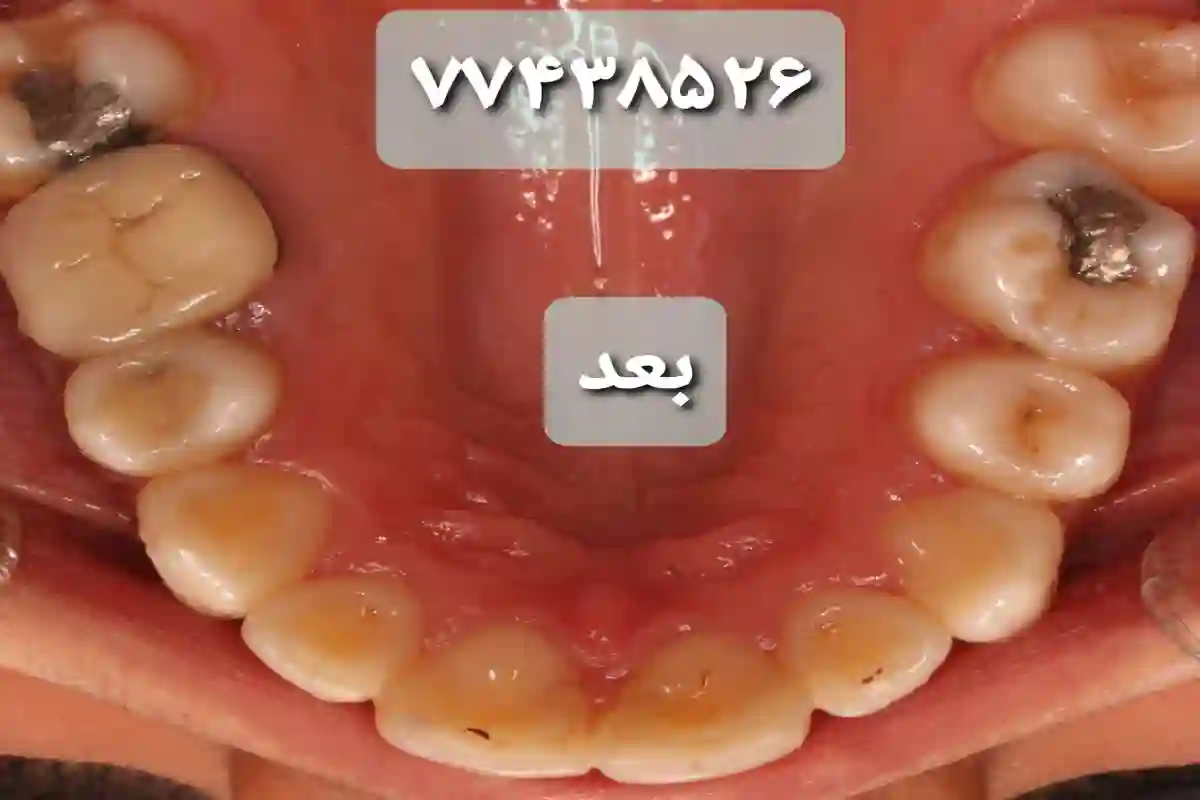

دکتر نگاه بازقلعه متخصص ارتودنسی با بیش از ۱۰ سال تجربه بالینی انواع ناهنجاری های دندانی و فکی را درمان میکند. در کلینیک ارتودنسی دکتر نگاه بازقلعه خدمات ارتودنسی صفر تا صد توسط متخصص انجام میشود در این کلینیک خدمات ارتودنسی به صورت کاملا اقساطی انجام میشود و نیاز به هیچ پیش نیاز و چک و یا سفته نمیباشد انواع ارتودنسی شامل :ارتودنسی نامرئی (الاینر)،ارتودنسی پیشگیری،ارتودنسی کودکان، ارتودنسی بزرگسالان ، اصلاح طرح لبخند، اصلاح ناهنجاریهای فک و صورت،ارتودنسی شفاف و … انجام میشود. طرف قرار داد با بیمه های تکمیلی